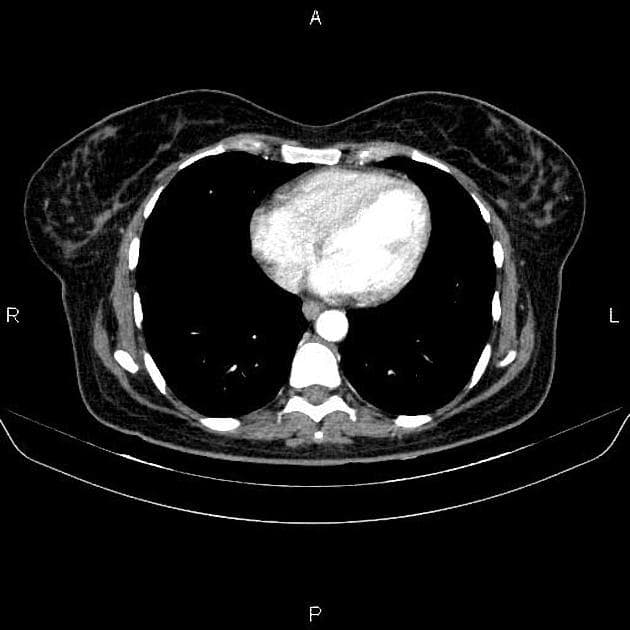

U nang ống mật chủ type III (Choledochocoele)

U nang ống mật chủ type III (Choledochocoele) trên hình ảnh chụp đường mật trong mổ và CT.

- Làm mờ hệ thống đường mật kèm giãn ống mật chủ ngoài gan.

- "Choledochocoele là dạng hiếm của u nang ống mật chủ type III, đặc trưng bởi giãn dạng nang đoạn ống mật chủ trong thành tá tràng."

- "Chẩn đoán xác định bằng các phương tiện hình ảnh như MRCP hoặc chụp đường mật nội soi, điều trị triệt để là cắt bỏ hoàn toàn để ngăn ngừa ác tính hóa."